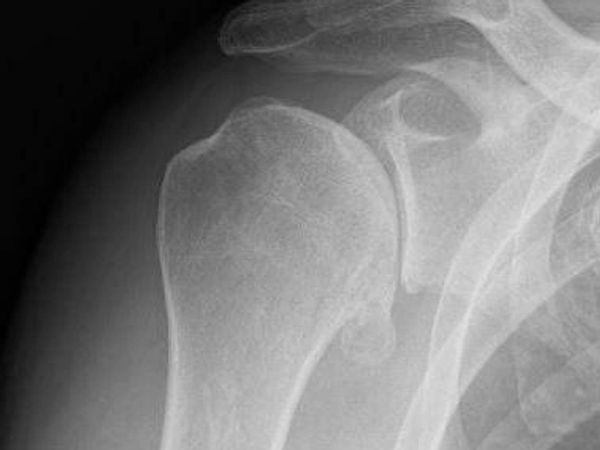

Examination reveals a mixture of positive subacromial, bicep and ACJ tests. Rotational movements in flexion create high sensitivity. X-rays are reported as normal, a recent US demonstrates some bursal thickening and no cuff tears visible. Posterior joint and suprascapular notch are clear. MRI shows some distal clavicle edema, no cuff tear, type II acromion and no obvious labral pathology.